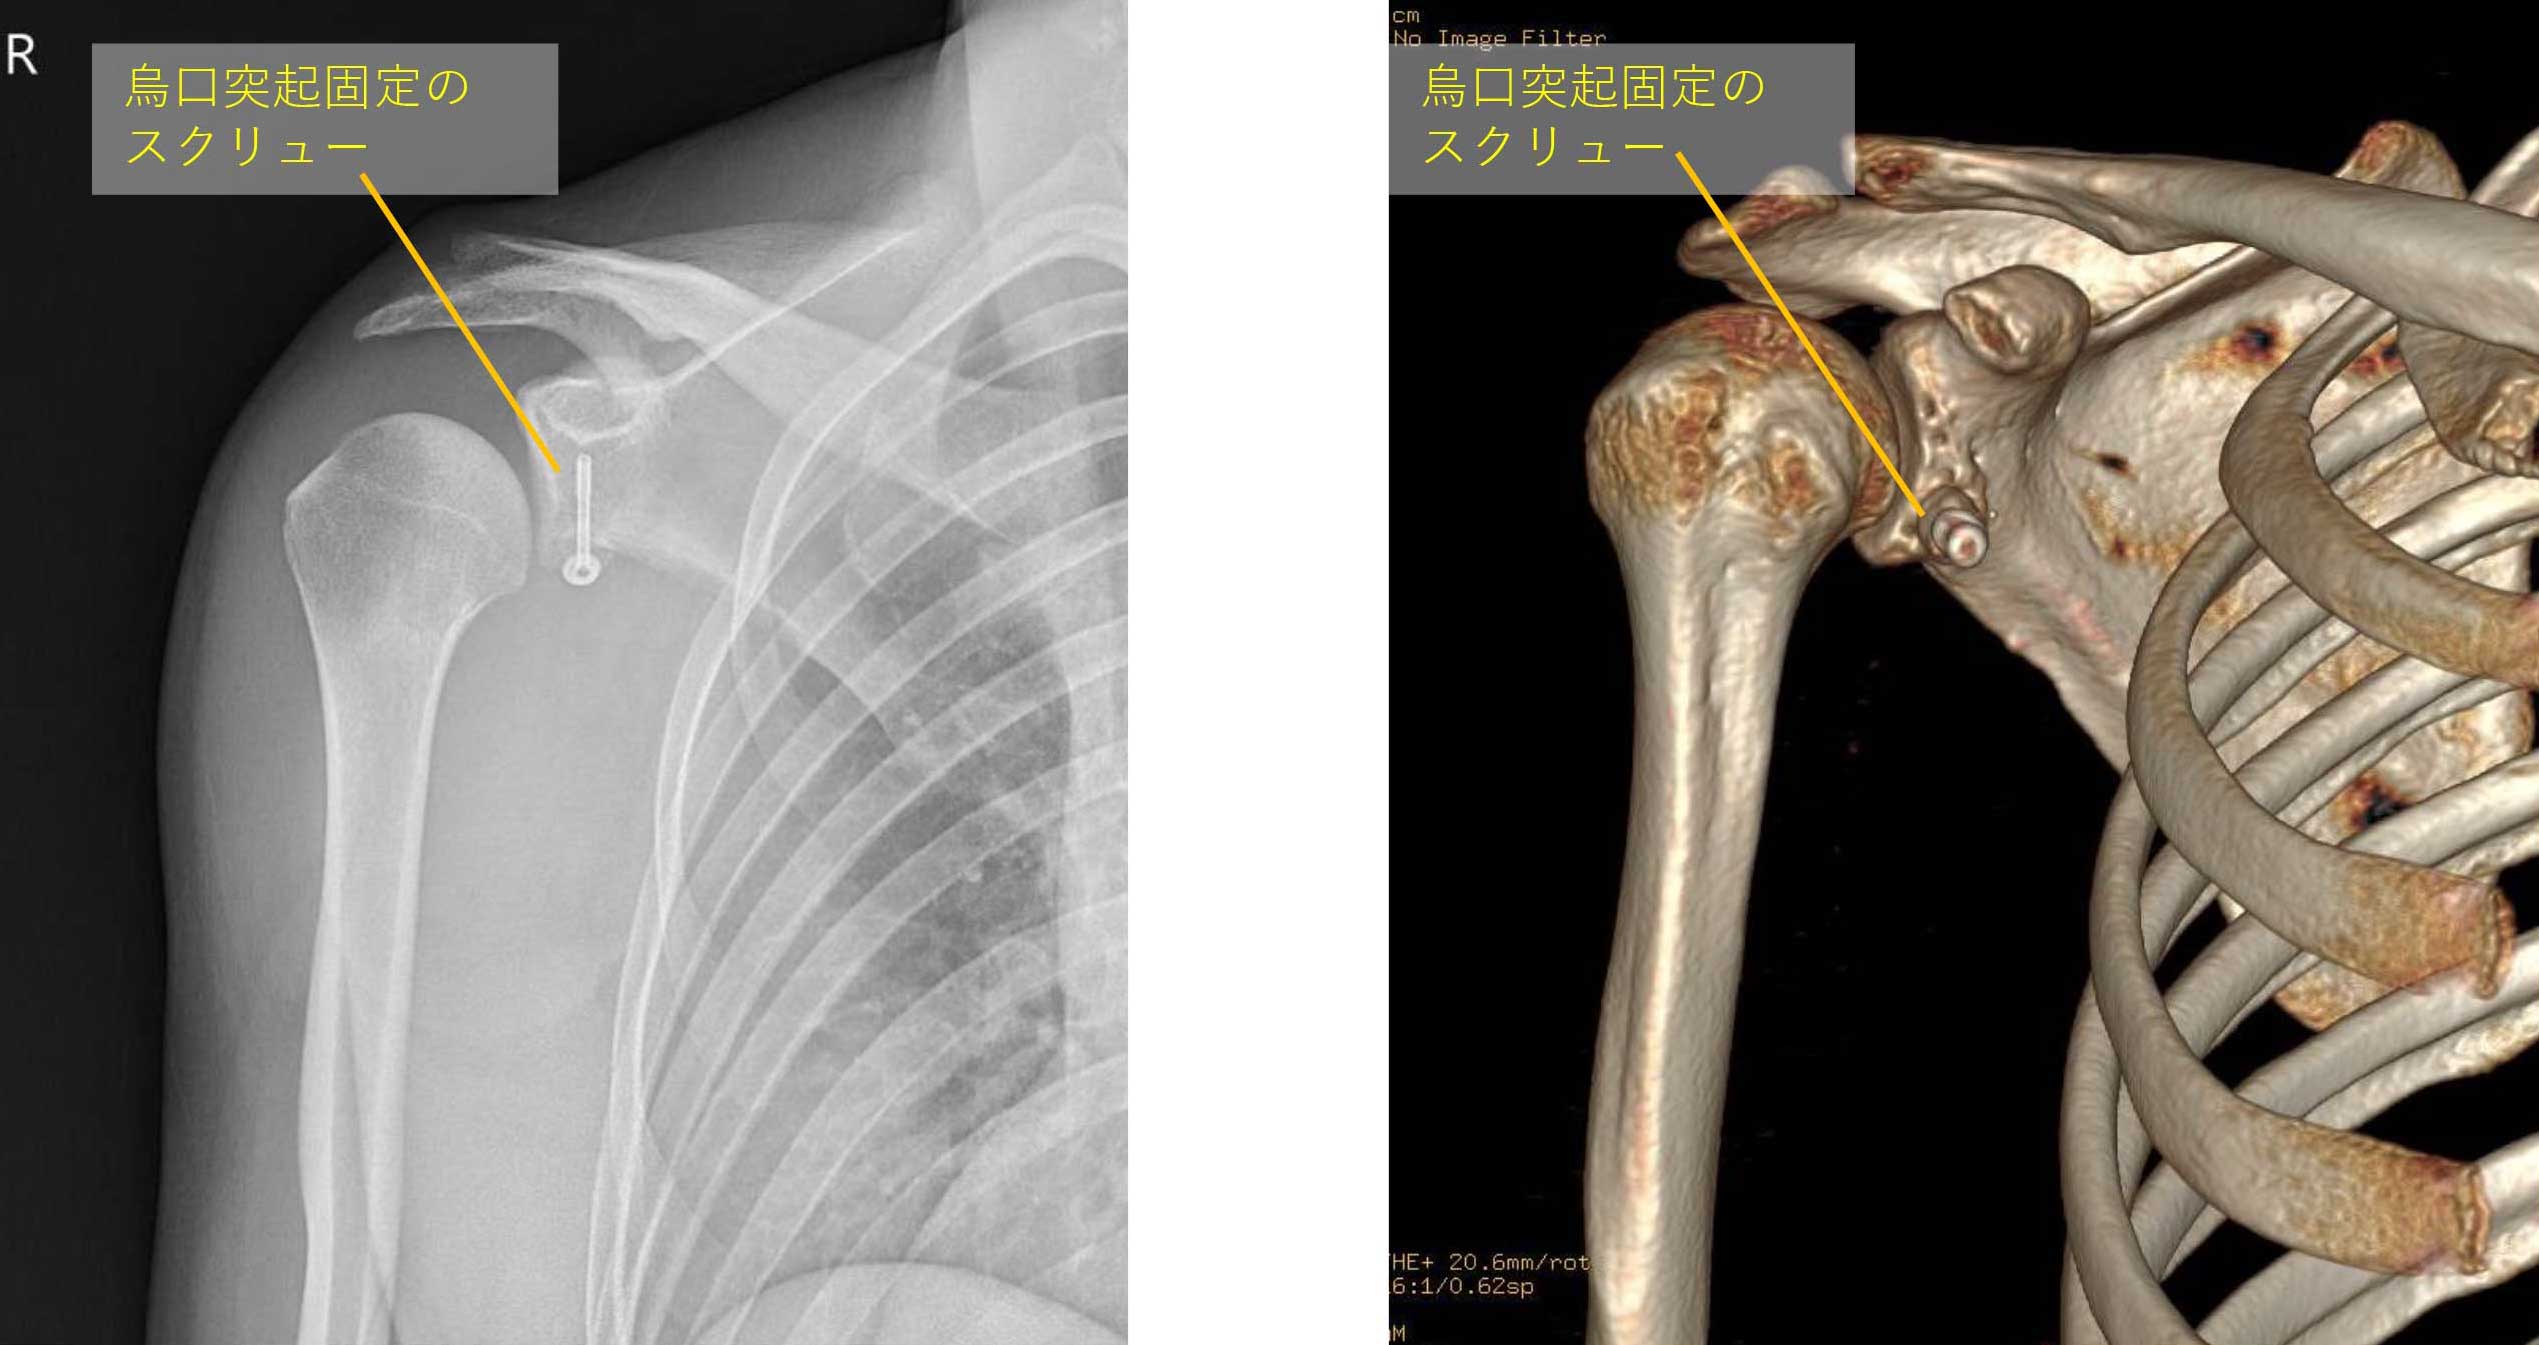

②鏡視下バンカート&ブリストウ法

鏡視下バンカート&ブリストウ法術後のレントゲン・CT

骨を移植することでより強固に脱臼を制動する手術です。鏡視下バンカート法を行っても再発した場合や、ラグビー・アメリカンフットボール・柔道などのコンタクトスポーツ選手、自衛隊員・レスキュー隊員などの危険業務に携わる方の場合にはこちらを行います。競技までの復帰が早いことも特徴です。

・烏口突起(骨)を腱をつけたまま切る。

・烏口突起を関節窩の前にスクリューで固定。

・鏡視バンカート修復術を行います。